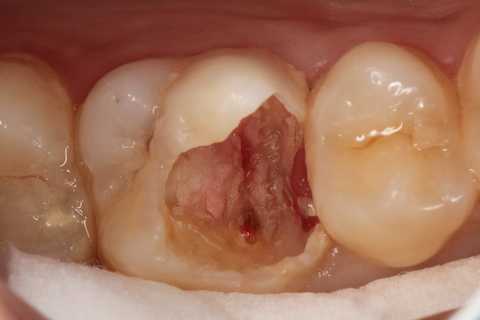

20代女性、左上6、自発痛+

確かに窩洞内はプラークまみれで、露髄しているので痛いのだろうな。。と思わせる。

でも、露髄していようが、感染歯髄だろうが、歯髄息肉だろうが関係ない。歯髄があるところまでα-TCPセメントで塞げば、痛みも止まるし、歯髄を保存できる。

次回はちゃんと充填して歯を作るからねーと言って仮封して帰ったが、痛みが止まったので、もうこれでいい!と勝手に判断して来ない。電話をかけても出ない。知らんわ、、

では時系列でどうぞ